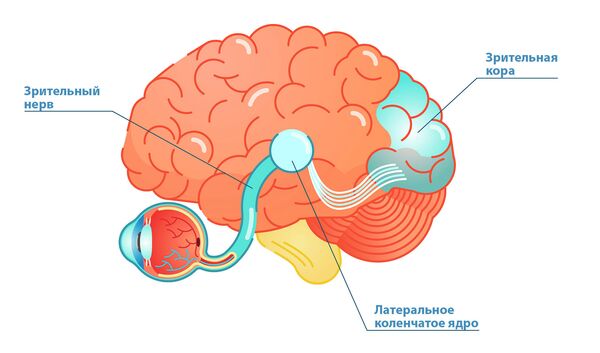

Схема чувствительных зон новой коры мозга